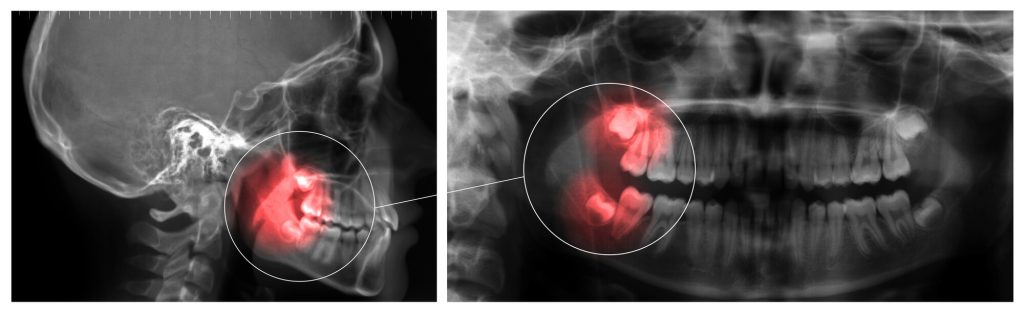

Wisdom Teeth Issues

Usually appearing in late adolescence or early adulthood, wisdom teeth can frequently cause issues. Their position at the back of the mouth may cause them to become impacted, which prevents them from fully emerging from the gum line. This can cause infection, pain, and harm to the surrounding teeth over time.

To prevent that, wisdom teeth are often removed.